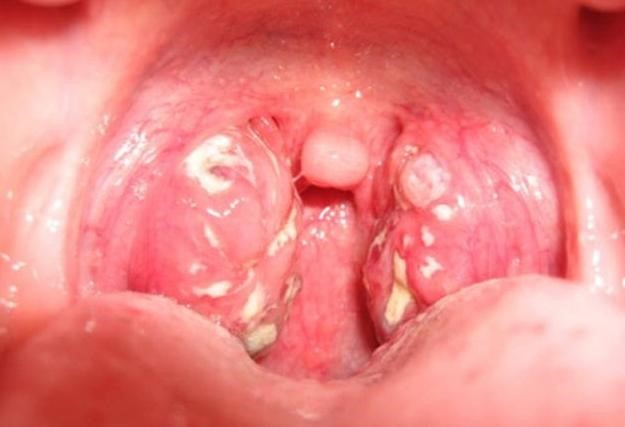

Казеозные пробки в горле представляют собой гнойные образования в результате гибели клеток, лейкоцитов и бактерий. На вид и по консистенции напоминают творог белого, желтого или серого цвета. Заполняют они ниши в миндалинах, называемые лакунами. При внешнем осмотре с помощью зеркала их можно легко увидеть. Иногда они чувствуются при глотании, создавая ощущение инородного предмета в горле.

- Казеозные пробки также являются основным признаком острого тонзиллита (ангины). При фолликулярной и лакунарной ее формах на миндалинах образуется гнойный налет, называемый пробками. Эти пробки и вызывают сильный воспалительный процесс, повышение температуры, общую интоксикацию организма. После комплексного и своевременного лечения (обычно без антибиотиков не обойтись) лакуны очищаются от гнойного налета и человек полностью выздоравливает.

Казеозные пробки, в первую очередь, видны при поверхностном осмотре. Если есть ощущение, что что-то мешает в горле, нужно взять зеркало и заглянуть в ротовую полость. Небольшие бугорки на поверхности небных миндалин с белым или желтоватым содержимым и есть пробки. Чаще всего они появляются при заражении острой формой тонзиллита. Тогда, кроме гнойного налета, будут присутствовать и другие характерные симптомы: